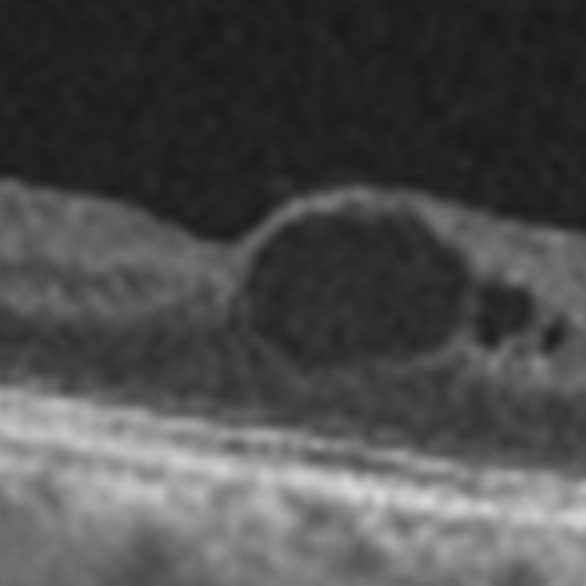

近年、眼科の診療機器はめざましく進歩し、顕微鏡で覗くように眼球の細部まで観察できるようになってきました。当科ではこうした最新機器を多数導入し、できる限り多くの情報をもとに診断を行っています。検査結果の多くは電子カルテ上で患者さんご自身にもご覧いただけるため、眼の状態をしっかり理解した上で治療を進めることができます。